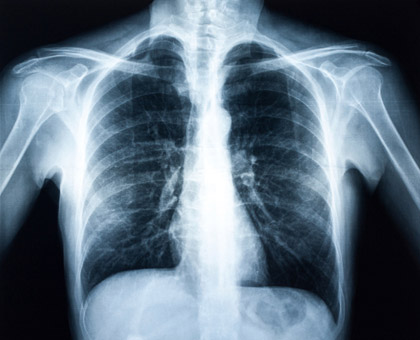

La consommation de tabac a chuté de plus de 15% chez les hommes en France depuis le milieu des années 1980, alors qu'elle a légèrement augmenté chez les femmes, selon les résultats de l'enquête MONICA menée par des chercheurs français. Publiés dans l'édition de décembre de la revue scientifique European Journal of Cardiovascular Preventio... Lire la suite